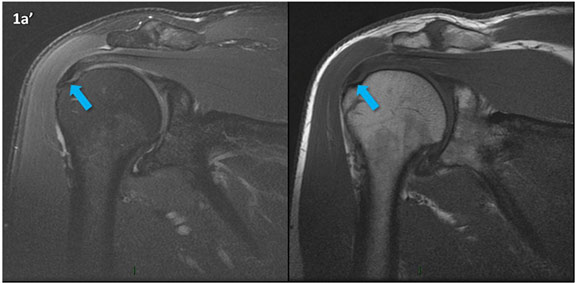

Figura 1 (a-g): Imagens consecutivas de RM no plano coronal nas ponderações DP com supressão de gordura (DP SG) à esquerda e T1 à direita. Clique na seta para passar as imagens.

Figura 1 (a-g)': Imagens consecutivas de RM no plano coronal nas ponderações DP com supressão de gordura (DP SG) à esquerda e T1 à direita mostrando . Clique na seta para passar as imagens.

Figura 1a’ mostrando rotura parcial articular na inserção do supraespinhal (setas azuis).

Figuras 1b’ a 1g’ mostrando atrofia da porção superior do músculo redondo menor (seta salmão), com lipossubstituição mais evidente das mais fibras laterais (seta amarela). As fibras mais inferiores e mediais têm atrofia menos evidente.

Repare que estas alterações não são evidentes nas imagens com supressão de gordura.